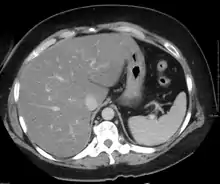

في التصوير المقطعي المحوسب (CT)، سيحد محتوى الدهون الزائد من كثافة أنسجة الكبد، مما يجعل الصورة أقل سطوعًا. عادةً تكون كثافتا الطحال والكبد متعادلتين تقريبًا. في التنكس الدهني، هناك فرق بين الكثافة وسطوع العضوين، حيث يظهر الكبد أكثر قتامة.[10] على جهاز الموجات فوق الصوتية، تبدو الدهون أكثر مولد للصدى (قادرة على عكس الموجات الصوتية). كما أن تركيبة التنكس الدهني للكبد قاتمة على الصور المقطعية المحوسبة وساطعة على جهاز الموجات فوق الصوتية، مما يعرف أحيانًا بعلامة تخبط الوجه.